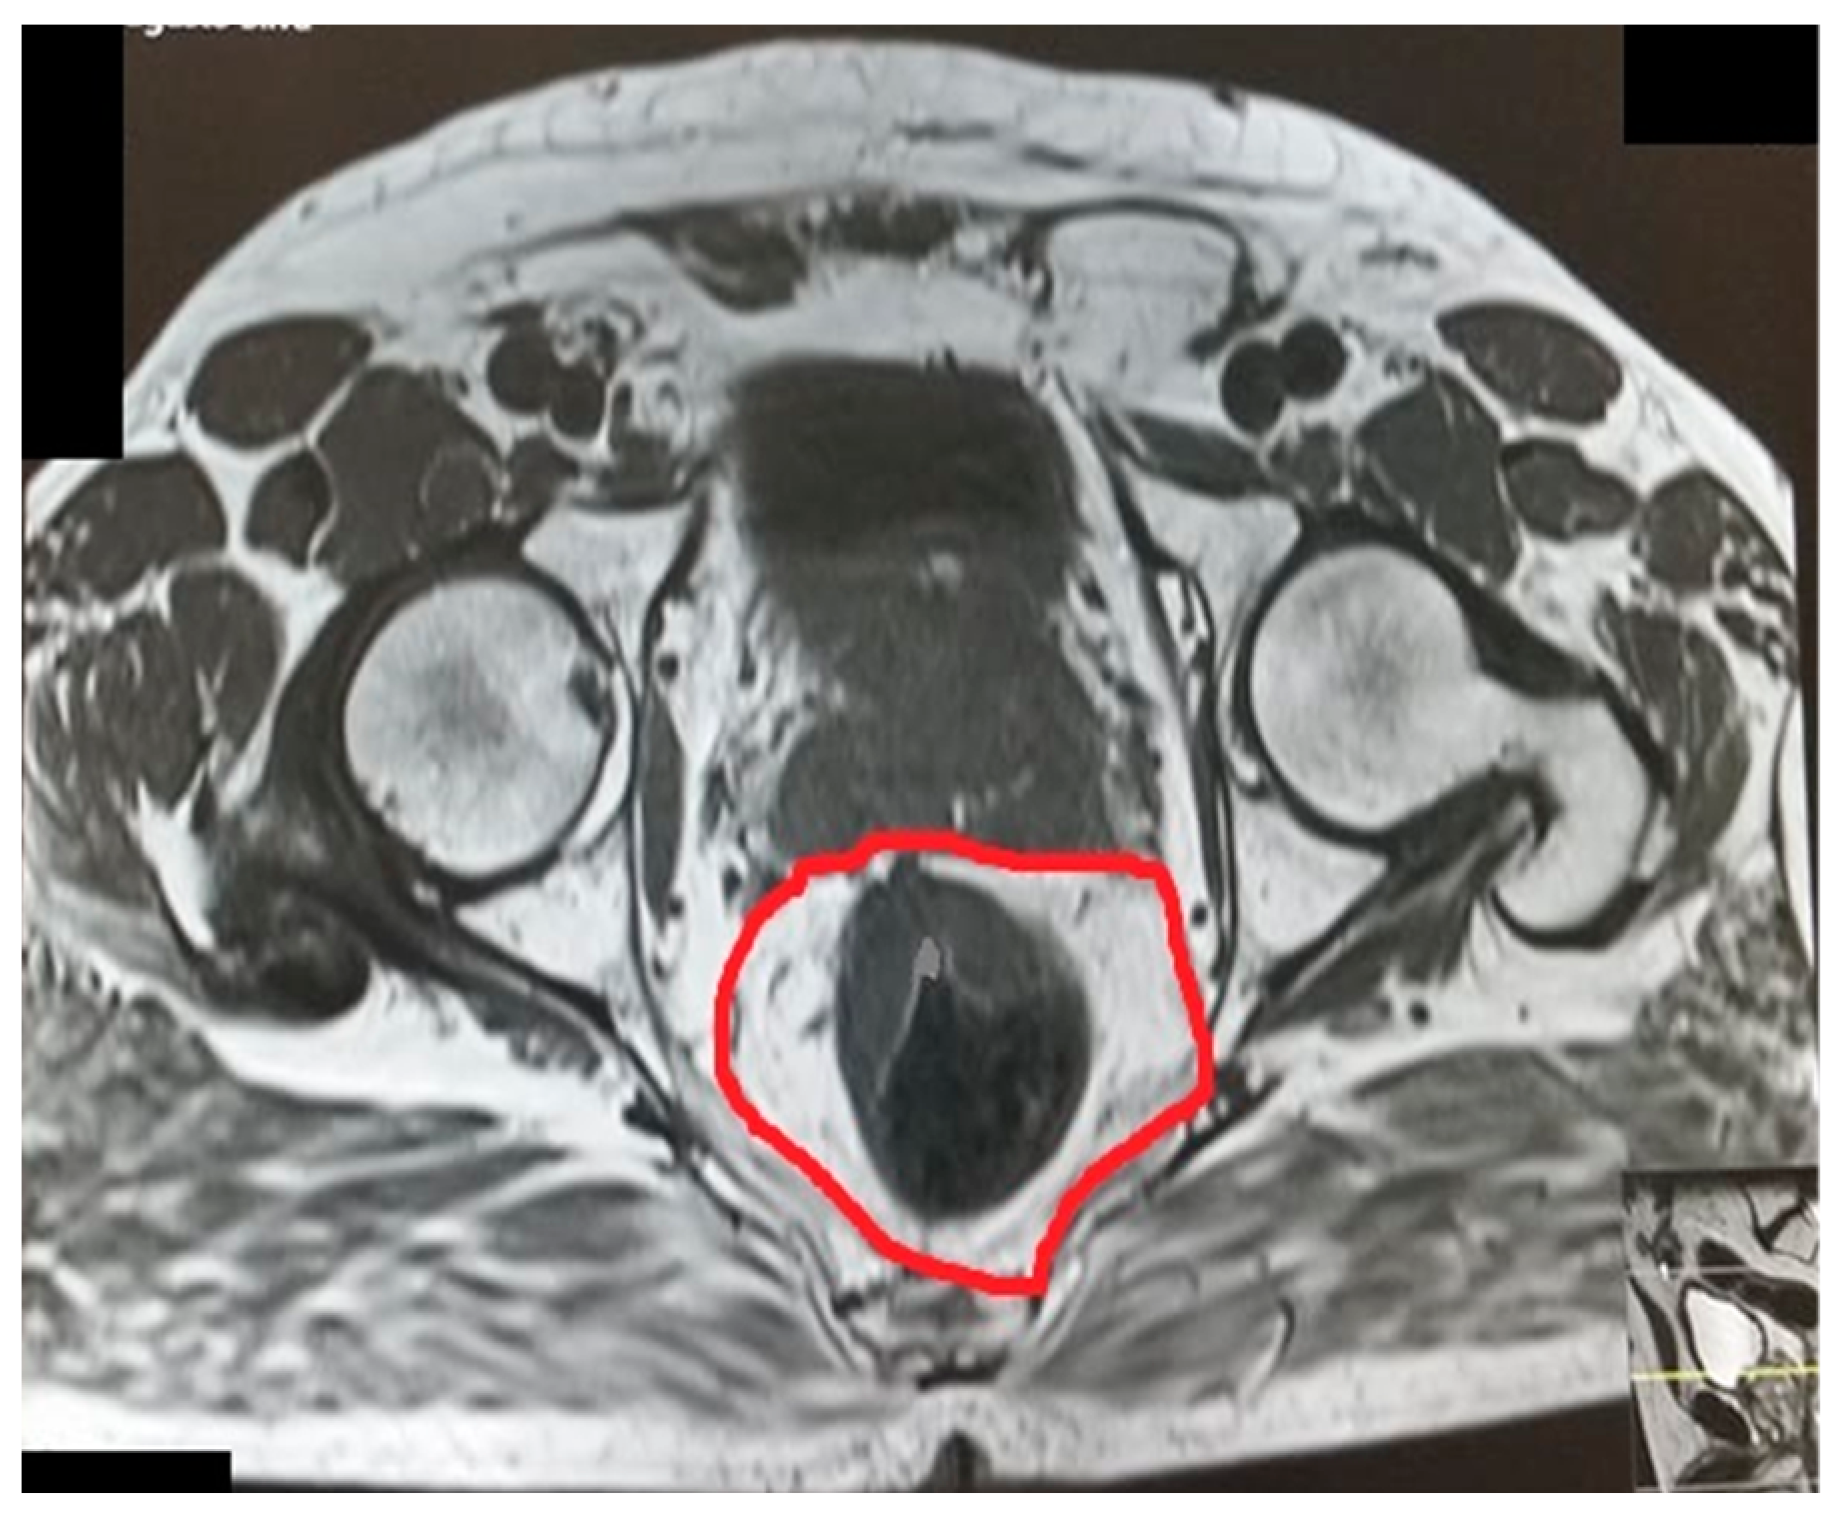

Figure 6.

Rectal area.